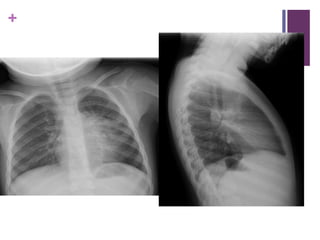

Inhaled Foreign Body

 Esp 1-3yo incomplete chewing, food propelled

posteriorly, triggers reflex inhalation

 Most foreign bodies are radiolucent; need indirect

radiologic findings

 Hyperinflation from ball/valve effect in affected lung

 CXR 70%-80% sensitive, (50% airtrapping, 12%

atelectasis, 18% infection) if N and high index suspicion -

Bronchoscopy

 Can use CT